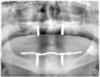

Wasja Опубликовано 3 декабря, 2012 Поделиться Опубликовано 3 декабря, 2012 На днях пришла такая вот радость...Сдал работу год назад. Теперь чешу репу, что делать... Ссылка на комментарий

geguli4 Опубликовано 4 декабря, 2012 Поделиться Опубликовано 4 декабря, 2012 На днях пришла такая вот радость...Сдал работу год назад. Теперь чешу репу, что делать... Ну а что тут катастрофичного?!?!В принципе,более-менее закономерный исход...Ну чуть раньше чем обычно... Ссылка на комментарий

geguli4 Опубликовано 4 декабря, 2012 Поделиться Опубликовано 4 декабря, 2012 А почему наверху в одном аттачмент,а во втором заглушка? Ссылка на комментарий

Wasja Опубликовано 4 декабря, 2012 Поделиться Опубликовано 4 декабря, 2012 По моему опыту подобные работы достаточно стабильны 5-6 лет. Конечно, расположение замков не самое оптимальное, но все же... Во втором имплантате сверху локатор. Верх ставил не я. Ссылка на комментарий

geguli4 Опубликовано 4 декабря, 2012 Поделиться Опубликовано 4 декабря, 2012 Интересно.Тогда думаю надо попытаться обследовать пациента.Сахар,щитовидка...Какие-то инфекционные дряни... Ссылка на комментарий